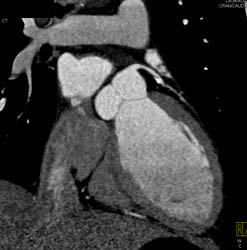

Plaque in LAD